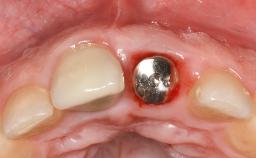

Mauricio Araujo and Flauvia Matarazzo present this straightforward clinical case, demonstrating the potential effect of implant placement depth on the resolution of peri-implant treatment. A 42-year-old systemically healthy female patient, a non-smoker with no history of periodontitis, was treated at the Dental Clinic at the State University of Maringá, Brazil between 2008 and 2009, when she received five implants restored with single crowns at sites 14, 26, 27, 36, and 46. After delivery of the implant-supported prosthetic restorations, the patient was enrolled in the supportive peri-implant therapy (SPiT) maintenance program at the same university.